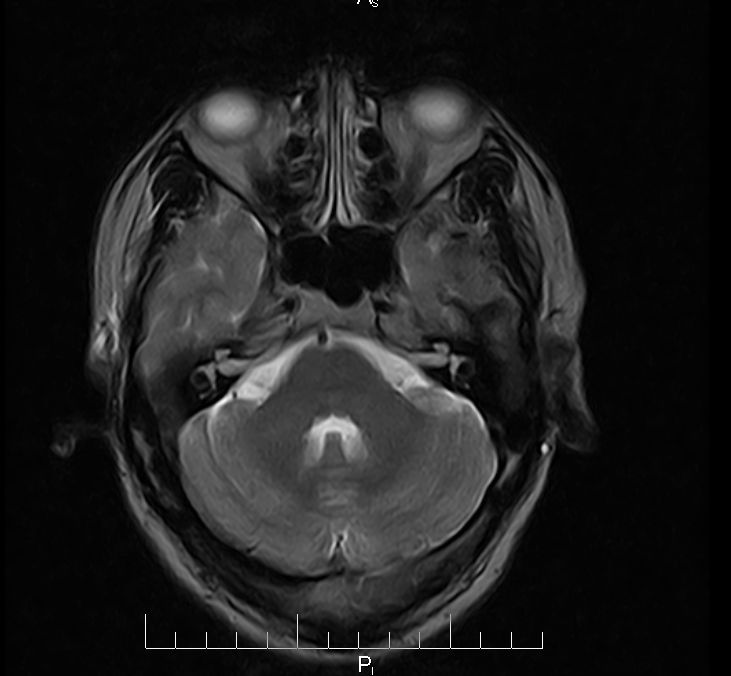

标题: MRI2379:30岁,男,癫痫10年,请各位看一下;CT示:左颞叶钙 [打印本页]

标题: MRI2379:30岁,男,癫痫10年,请各位看一下;CT示:左颞叶钙

左颞叶区见不规则点状混杂信号影

支持2楼 左颞叶区见不规则点状混杂信号影,考虑动静脉畸形。

考虑左侧颞叶脑血管畸形(avm)。----t1低等高混杂信号,t2等高信号周边较多流空血管影[冠状位明显],mra左侧大脑中动脉受压,远侧聚集.